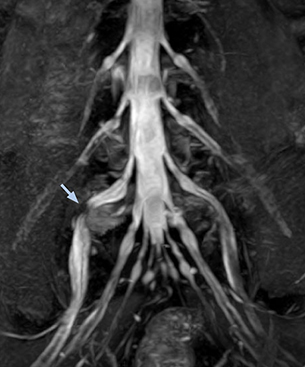

At Northern Fukushima Medical Center in Japan, excellent MRI visualization of nerves helps support confident diagnoses and informs surgical treatment decisions for patients with lower limb symptoms. MRI technologist Tanji and orthopedic surgeon Dr. Yabuki share how direct nerve visualization with the 3D NerveVIEW method adds information when diagnosing atypical herniations. The additional insights changed their way of working and benefit their patient care, as illustrated by some clinical examples.

“In patients with lower extremity neurological symptoms, NerveVIEW helps us to determine the disease matching the patient’s symptoms by directly visualizing the nerves. We use the sequence mainly, when there is suspicion of intraforaminal stenosis, extraforaminal stenosis or lateral disc herniation, which is often based on routine T2- and T1-weighted images. Additionally, the excellent depiction of the course of nerves makes NerveVIEW a good navigator when applying treatment such as block therapy or surgery.”

“In such case, we would then browse through axial T2-weighted MR images slice by slice and mentally reconstruct the actual situation based on both radiculography and MRI. Fortunately, NerveVIEW can now very well show nerve courses and presence of nerve compression or edema in one single image series.” “We have often seen NerveVIEW directly depict details of the nerve compression that were not observed by radiculography. Therefore, we think that with NerveVIEW we can reduce the number of invasive examinations, especially for some patients with lumbar plexus symptoms.”

The key concept in MR neurography, Dr. Yabuki stresses, is the ability to directly visualize spinal nerves, versus inferring the presence of pathology indirectly. “Before NerveVIEW, we estimated compression of the nerve by looking for the presence or absence of fat signal on other MR images,” he says.

“For example, in sagittal images, when the presence of fat is observed in the intervertebral foramen, it suggests that there is a margin around the nerve. Similarly, the absence of fat indicates that the nerve is being compressed. So, we used to deduce nerve compression indirectly. With NerveVIEW, however, we can observe the condition of the nerves directly, regardless of the presence or absence of fat. We always prefer such direct observation of anatomy over having to make an inference about it.”

“Although symptoms of typical disc herniation and atypical hernia are very similar, the actual site of herniation is different. It is therefore important to characterize the nerve’s condition both inside and outside of the intervertebral foramina. “Conversely, if we see no abnormality in NerveVIEW, we can assume at least that there is no severe condition that requires surgery. Like this, it can help us avoid unnecessary surgery. NerveVIEW can have a tremendous impact in this way.”

“NerveVIEW is really useful for those cases where a nerve disorder is strongly suspected based on the clinical examination but our regular MRI images do not show any findings. These atypical herniations and spinal canal stenosis, occurring in 5% to 15% of the total lumbar herniation/stenosis cases are our main target when using NerveVIEW,” says Dr. Yabuki.